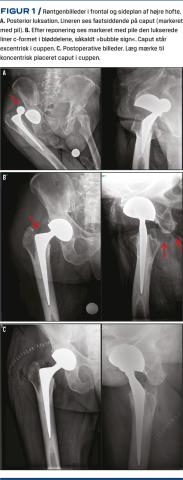

En 83-årig kognitivt velbevaret mand fik pga. hofteartrose isat en højresidig THA med DMC på et regionshospital. Operationen og efterforløbet var ukompliceret. Fem uger senere opsøgte han en skadestue på et andet regionshospital, da han havde smerter omkring højre hofte. Han havde siddet på et toiletbræt og bøjet sig ned for at smøre fødder, hvilket medførte dyb fleksion samt indadrotation og adduktion i den opererede hofte og resulterede i smerter og immobilisering. En røntgenoptagelse af højre hofte viste bagerste hofteluksation (Figur 1A). På skadestuen blev hoften reponeret i rus med pethidin og stesolid, og den efterfølgende røntgenoptagelse af hoften blev vurderet som normal. Patienten blev indlagt på en medicinsk afdeling pga. svimmelhed i dagene op til luksationen. Til næste dags røntgenkonference blev det konstateret, at caput stod excentrisk i cuppen, og at lineren ikke var på plads (Figur 1B), et såkaldt bubble sign [4]. Patienten var i velbefindende og uden tegn på neurovaskulær påvirkning i højre underekstremitet. Han blev opereret dagen efter, hvor lineren kom frem i operationsfeltet ved gennembrydning af fascien. Liner og caput blev udskiftet, og halslængden blev øget for at give mere stabilitet (Figur 1C). Forløbet efter revisionen var ukompliceret.

IPD efter primær THA med DMC er et sjældent, men kendt fænomen. Oftest ses det pga. mange års slid på lineren og hos revisionshofterne [3-5]. Der skal store kræfter til at disintegrere lineren fra caput, da denne under operationen mekanisk bliver presset ned over caput under brug af store kræfter. En ukorrekt samling vil kunne give IPD ved luksation, og lineren bør derfor ses på caput på en røntgenoptagelse, inden man forsøger en lukket reponering. Da røntgenoptagelser ikke altid afslører den lukserede liner, kan en CT derfor være relevant til præoperativt at identificere linerens placering. IPD kan aldrig reponeres lukket og kræver altid kirurgisk intervention, og hvis caput er excentrisk placeret i cuppen, bør man få mistanke om IPD.